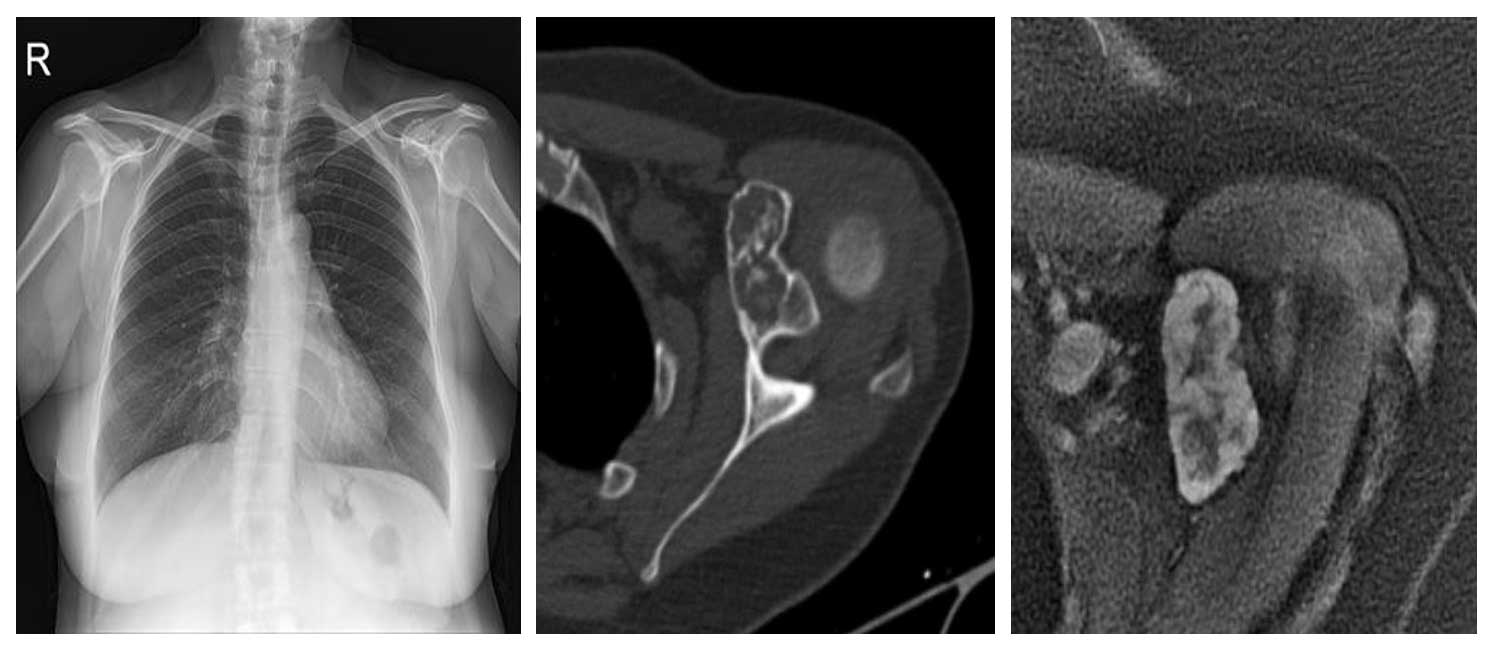

Genç erkek hasta, omuz ön bölümünde uzun süredir devam eden ağrı ve hareket kısıtlılığı şikayetleri ile başvurmuş; yapılan görüntüleme ve biyopsi sonucunda korokoid yerleşimli kondrosarkom tanısı doğrulanmıştır.

Ameliyat Öncesi: Röntgende korokoid üzerinde düzensizlik, tomografide genişleme, kortekste incelme ve kıkırdak dokusu, MR’da heterojen kitlenin boyutları görülmekte.

Ameliyat Sonrası: Röntgende korokoid eksizyonu yapıldığı, klavikulanın vidalar ile fikse edildiği görülmekte.